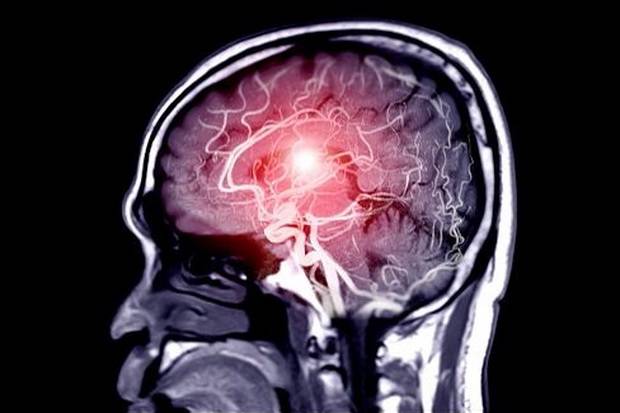

Penyakit ini merupakan kondisi di mana dinding pembuluh darah otak melebar atau menonjol (ballooning) akibat lemahnya dinding pembuluh darah tersebut.

Apabila aneurisma ini pecah dapat mengakibatkan kondisi fatal yaitu perdarahan otak (subarachnoid) dan kerusakan otak. Pecahnya aneurisma ini diperkirakan dialami oleh 1 orang setiap 18 menit.

Aneurisma otak dapat terjadi pada siapa saja, dan umumnya sebelum pecah aneurisma tidak bergejala, sehingga dianjurkan untuk melakukan brain check-up secara rutin.